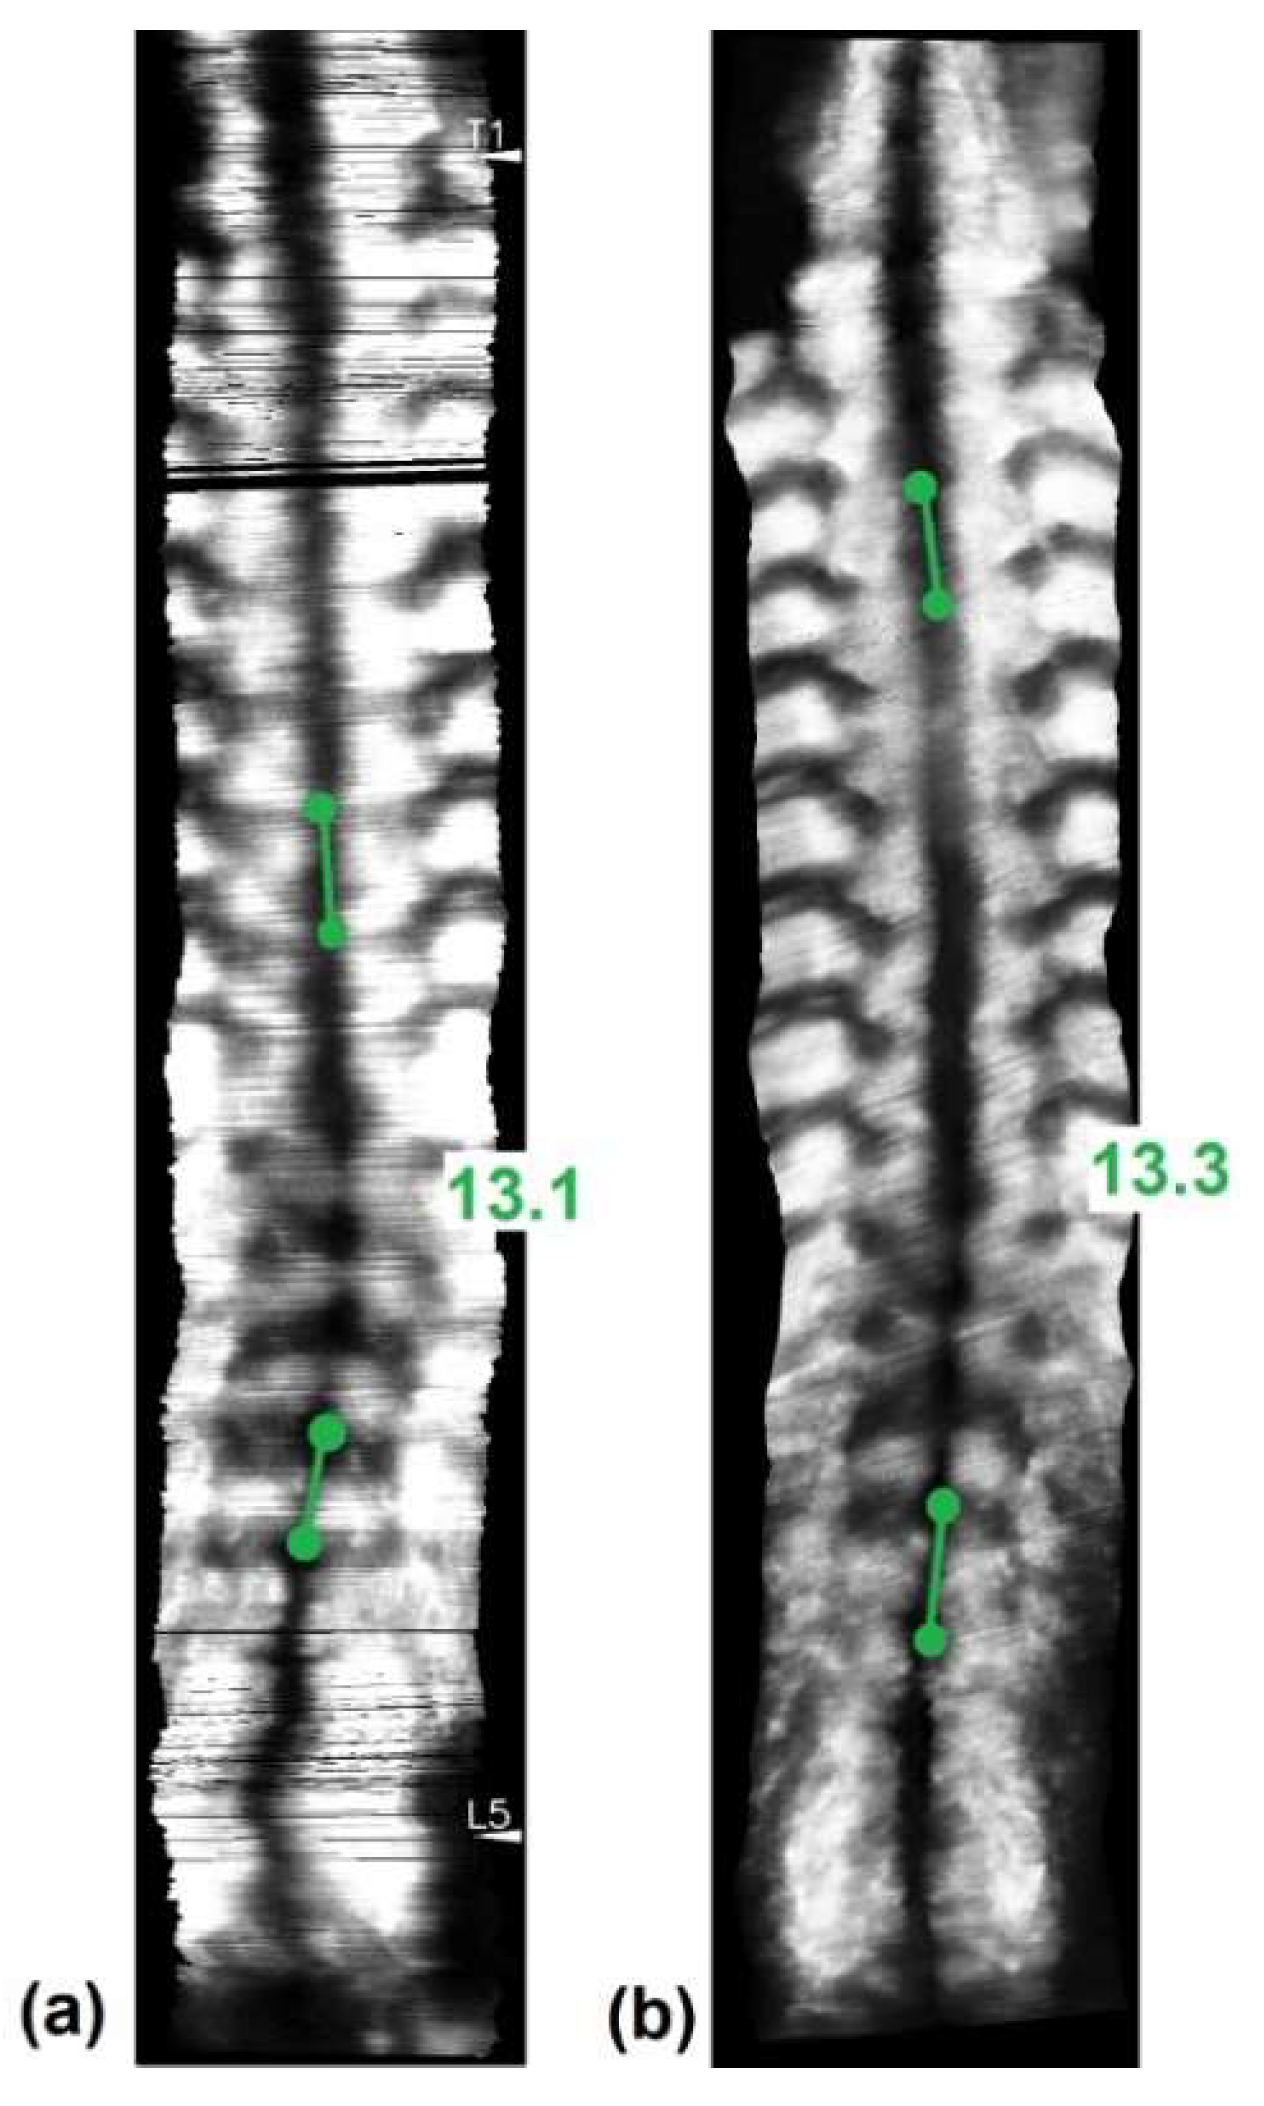

- Cheung, C.W.J.; Zhou, G.Q.; Law, S.Y.; Mak, T.M.; Lai, K.L.; Zheng, Y.P. Ultrasound Volume Projection Imaging for Assessment of Scoliosis. IEEE Trans. Med. Imaging 2015, 34, 1760–1768. [Google Scholar] [CrossRef]

- Zheng, Y.P.; Lee, T.T.Y.; Lai, K.K.L.; Yip, B.H.; Zhou, G.Q.; Jiang, W.W.; Cheung, J.C.W.; Wong, M.S.; Ng, B.K.W.; Cheng, J.C.Y.; et al. A reliability and validity study for Scolioscan: A radiation-free scoliosis assessment system using 3D ultrasound imaging. Scoliosis Spinal Disord. 2016, 11, 13. [Google Scholar] [CrossRef]

- Wong, Y.S.; Lai, K.K.L.; Zheng, Y.P.; Wong, L.L.; Ng, B.K.W.; Hung, A.L.H.; Yip, B.H.K.; Chu, W.C.W.; Ng, A.W.H.; Qiu, Y.; et al. Is Radiation-Free Ultrasound Accurate for Quantitative Assessment of Spinal Deformity in Idiopathic Scoliosis (IS): A Detailed Analysis With EOS Radiography on 952 Patients. Ultrasound Med. Biol. 2019, 45, 2866–2877. [Google Scholar] [CrossRef] [PubMed]